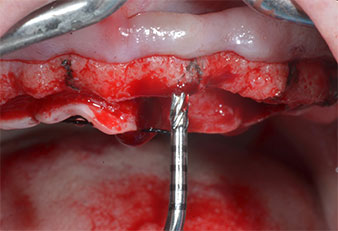

Due to the relatively hard bone (D2) in this area, the 10 mm long implant sites at positions 11 and 21 were finalized with a 4 mm diameter rotary drill, in combination with a W&H WS-75 L surgical contra-angle handpiece, the W&H Implantmed implant motor and the optional W&H Osstell ISQ module. In contrast, due to the soft bone the posterior sites were prepared to a final 3 mm diameter using the Piezomed I3P instrument. The implants were finally placed transgingivally to osseointegrate for three months (Figs. 6-10). The existing denture was retained on four provisional implants (Fig. 8).